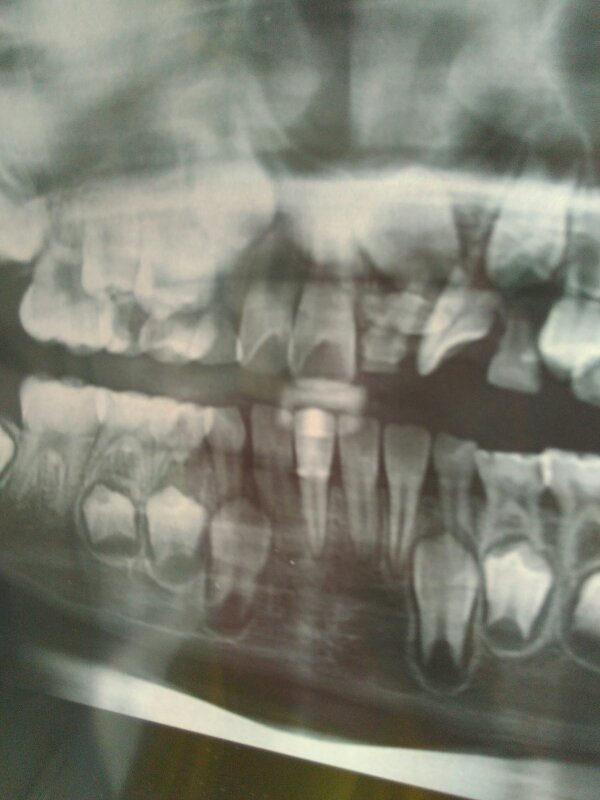

孩子2006年出生乳牙没退恒牙从影像上看一个横着长一个到着长 点击展开 匿名用户 2016-03-29 11:06 满意回答 你好,这种情况可以注意口腔卫生,注遮迷意补钙,不宜在长牙时舔牙龈躬缘了,也愿涌可以在长大一些后纠正治疗 ҹϸ258 2016-03-29 11:12 宝宝知道提示您:回答为网友贡献,仅供参考。 相关问题 乳牙未掉恒牙横着长在了牙床里 乳牙神经坏死打洞补影响出恒牙吗 你好我的孩子六岁恒牙被误拔了,8天了牙银还肿着要吃药吗?